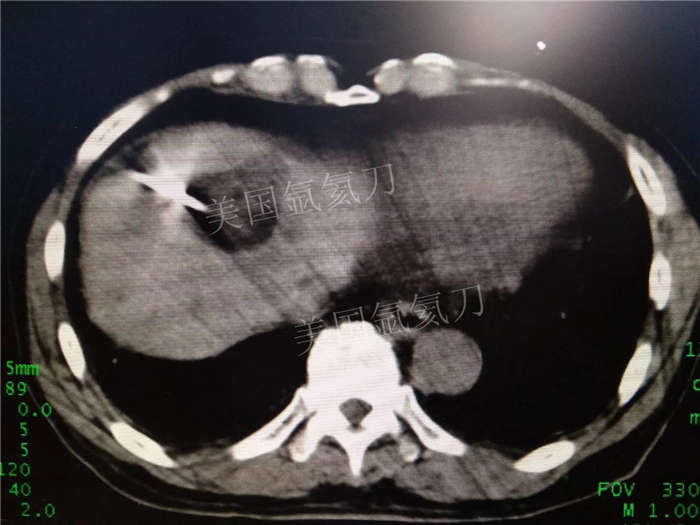

博罗人民医院乙状结肠癌术后肝转移化疗后冷冻消融